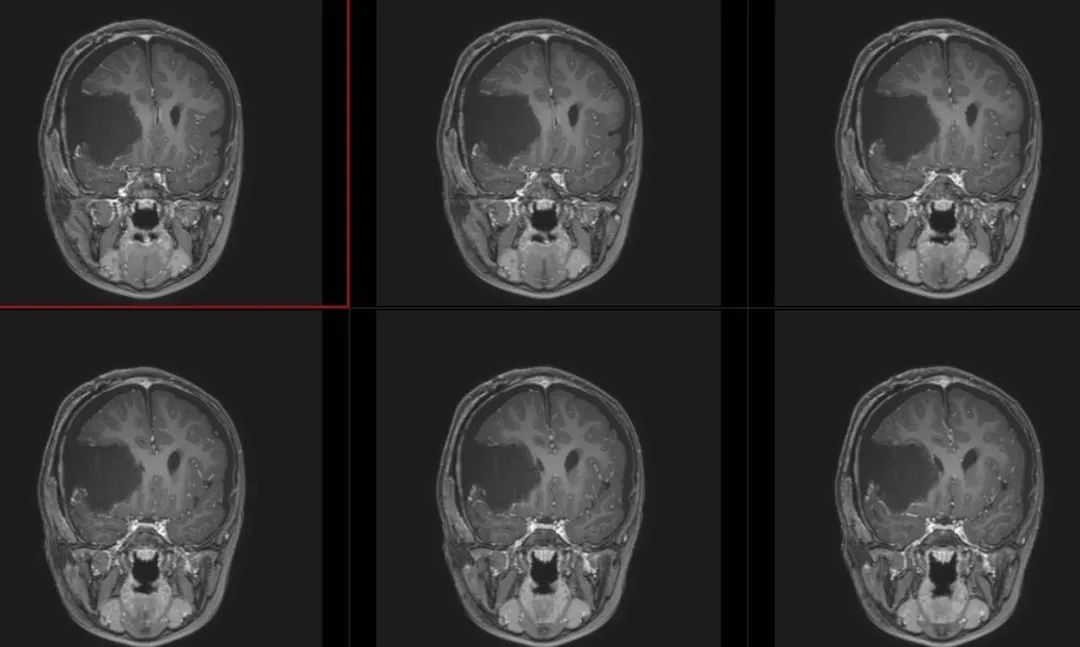

术前影像

术前T1冠状位

术前T1冠状位增强